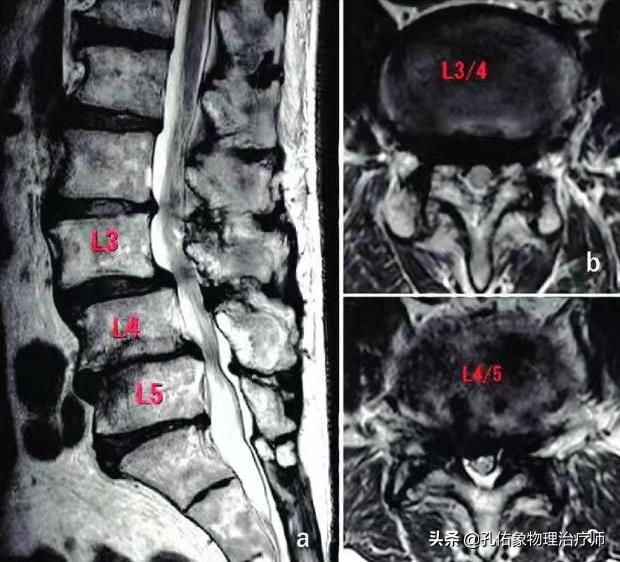

如上图中所示, 椎管在椎间盘(髓核+纤维环)的后方,里面穿行脊髓;若是因为某种因素使椎管变窄了,很可能会压迫神经、脊髓等。

腰椎的椎体后缘增生,后纵韧带的钙化,小关节突增生,侧隐窝狭窄,黄韧带肥厚,椎管内占位(肿瘤或间盘脱出)。

若是您的腰椎狭窄是椎间盘往后突出引发:说明间盘长期受到向后方的应力影响。

若是您的腰椎狭窄是黄韧带或后纵韧带的肥厚引发:说明长期的应力负荷造成拉扯致增生。

若是您的腰椎狭窄是关节突增生退变引发:说明关节上应力大,周边稳定的软组织弱。

若是您的腰椎狭窄是椎体滑脱引发:说明稳定结构差,保护椎体的结构丧失功能,椎体过度活动。